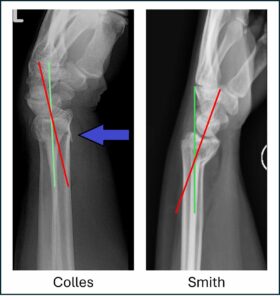

Colles – extraarticular with dorsal displacement and dorsal angulation, typically from fall onto extended wrist (Dinner Fork deformity).

Smith – extraarticular with volar displacement and volar angulation, typically from fall onto flexed wrist (Garden Spade deformity).